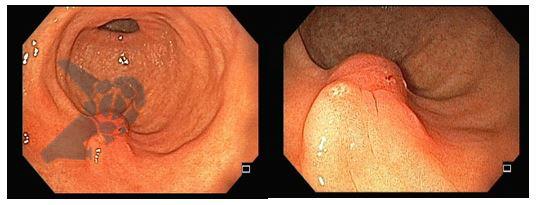

O laudo anatomopatológico revelou:

- Adenoma gástrico do tipo intestinal com displasia de baixo grau;

- Margens periféricas e profundas livres de displasia;

- H. pylori negativa

A endoscopia de controle 7 meses após o tratamento endoscópico revelou o seguinte achado (Fig. 3)